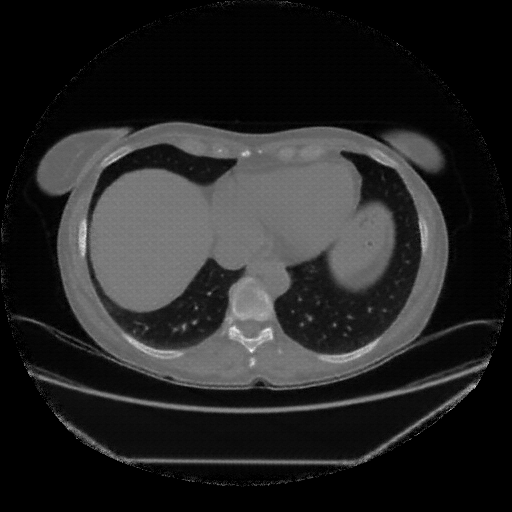

Image Grid

4Γ—3 grid: Rows show different image types (Original NATIVE, Reconstructed NATIVE, Original VENOUS, Generated VENOUS), Columns show windowing techniques (No Window, Lung Window, Mediastinum Window)

Generated VENOUS CT scan (A→B translation)

Lung window (WL -600, WW 1500 β†’ Low βˆ’1350, High +150)

Mediastinum window (WL 40, WW 400 β†’ Low βˆ’160, High +240)